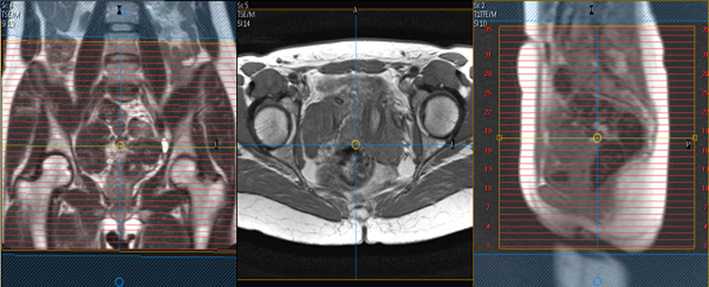

DYNAMICS Single slice. Place in the midline through pubic symphysis and coccyx. Center lower anal /vaginal canal.

MR Defecography WO BODY Protocol image 1